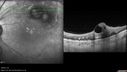

Self Sealed Retinal Arteriol Macroaneurysm468 viewsSD OCT line scan with intraretinal fluid

Self Sealed Retinal Arteriol Macroaneurysm456 viewsSD OCT line scan with intraretinal fluid

Self Sealed Retinal Arteriol Macroaneurysm452 viewsIR image shows MA on presentation